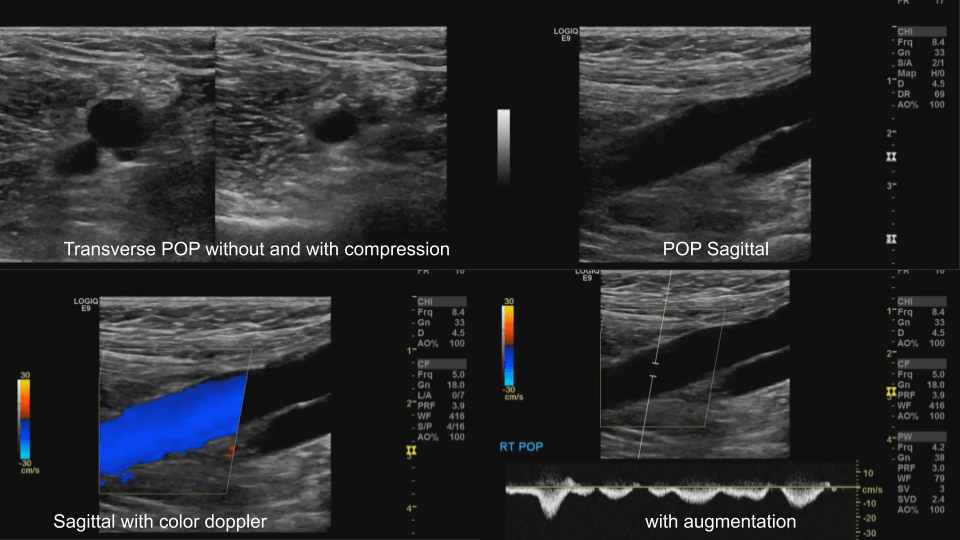

Popliteal Vein: Dual image with compression, greyscale, color doppler, color doppler and pulsed wave doppler